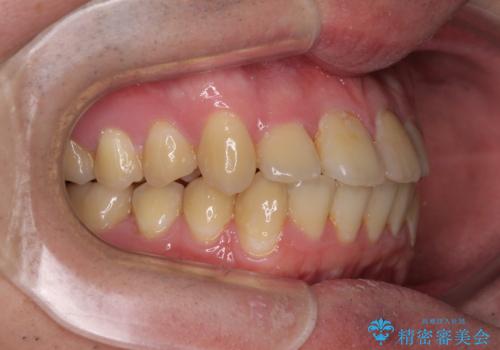

- 上下のデコボコと前歯のクロスバイトを改善したいとのことで来院された患者様です。

デコボコの程度は強かったのですが、口元の突出感はなかったため、非抜歯矯正としました。

クロスバイトは、治療の過程で咬み合わせが大きく変化する期間があり、食事が取りにくくなってしまいます。

また、装置が対合歯と咬み合ってしまい、頻繁に脱落するなど、色々と面倒なことがあり、治療がスムーズに進まないことがあります。